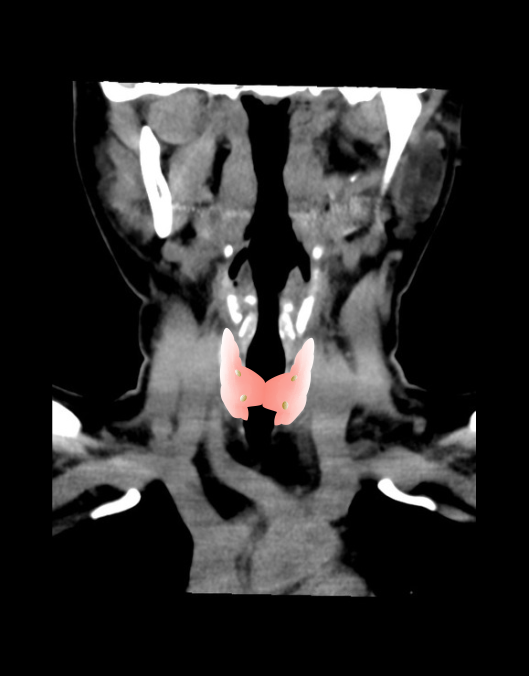

CT 4D neck scan is mainly used to diagnose abnormalities associated with the parathyroid gland, Specially, localizing parathyroid adenomas for surgeries. As it’s in the name, scan has 4 dimensions including 2D images, time (phases) and multiple planes.

- For all phases, plan the scan slab to cover from the skull base to the aortopulmonary window or carina.